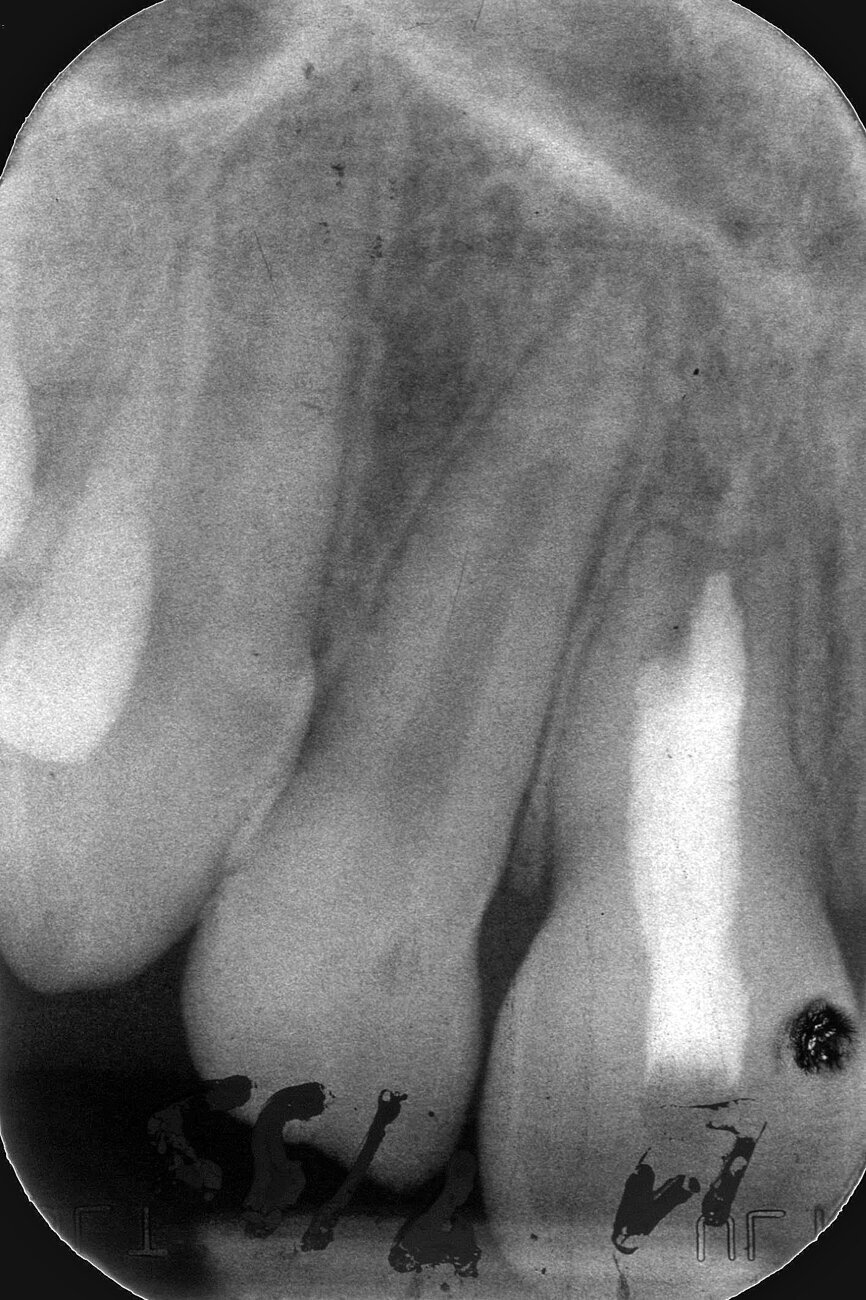

Case 2: Male (born 28 December 1980): Tooth 14

Fig. 4a: 18 August 1989 ante vitalextirpation.

Case 2: Male (born

28 December 1980): Tooth 14

Fig. 4b: 18 August 1989 post vitalextirpation.

Fig. 4c: 16 January 2004 status.